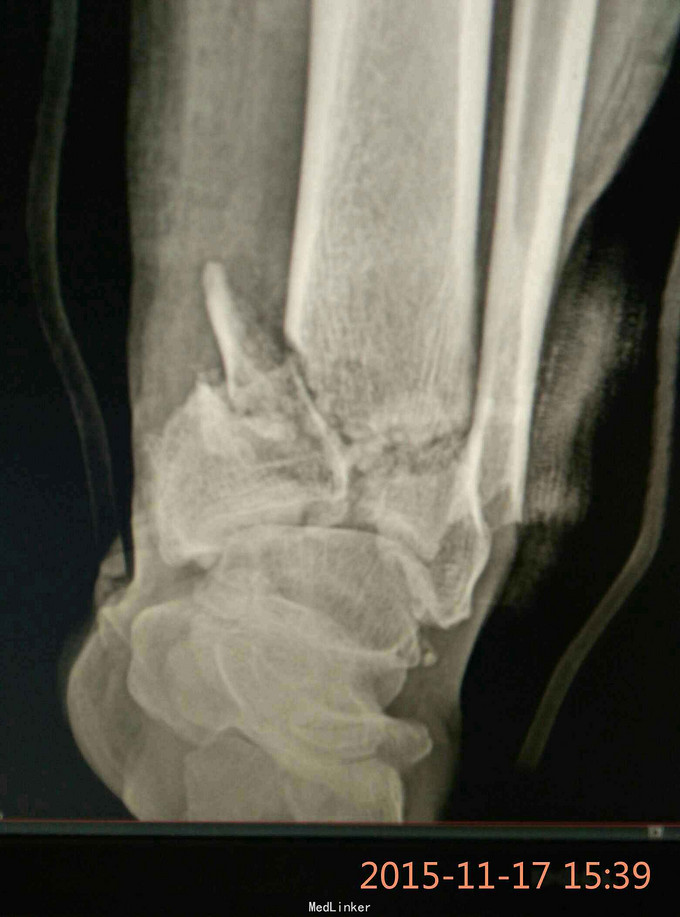

Pilon骨折,牵引10天

车祸致伤,开放性,急诊复位,跟骨牵引,清创,抗炎对症,伤口愈合可,无感染迹象,欲手术治疗,请各位老师给点建议。

伤时左踝畸形肿胀,外踝上方见长约5cm不规则裂伤,骨端外露,踝关节功能丧失,足背动脉搏动有力

左侧Pilon骨折于急诊清创骨折复位缝合并行跟骨牵引治疗。欲10天后,皮肤条件允许后,限期手术

选择何种术式,内固定物?